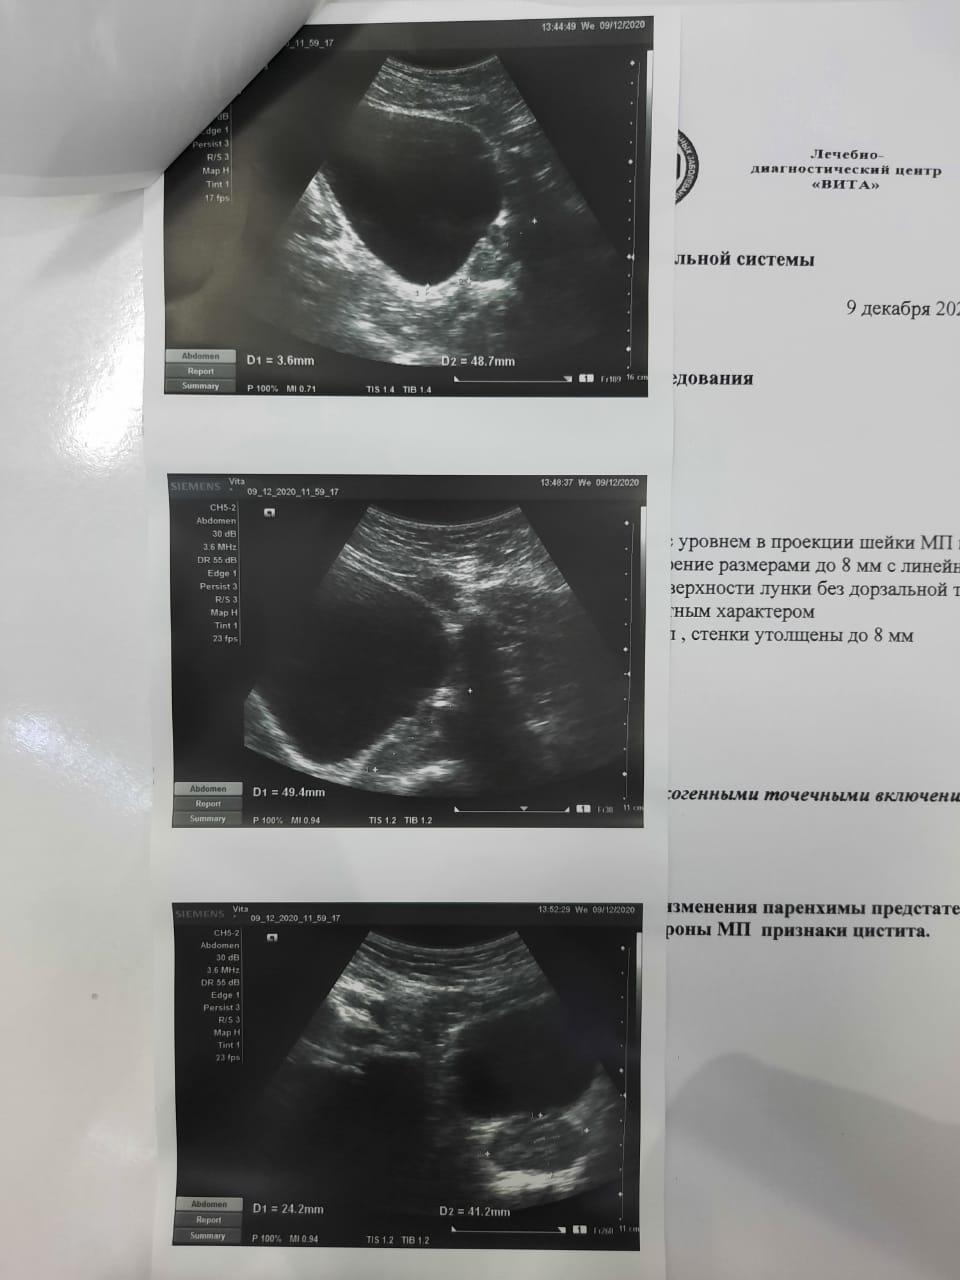

Застудил ноги, начал бегать в туалет, пошел в больницу, поставили диагноз хрон простатит и начали лечить, , лечили толку нет и после этого началась струя в разные стороны, сменил врача — то же самое, лечили простату. Мочевой не смотрели. Думали стриктура — сделали уретроцистоскопию, ее нет. Была чуть воспалена шейка. Сейчас обнаружили зппп, вылечили. Их нет. Симптомы остались, воспаления сняли. В узи выявили какую-то лунообразную впадину. Посмотрите пожалуйста, назначили лидазу/дистрептазу и амикацин. Анализы все чистые, флоры нигде нет.